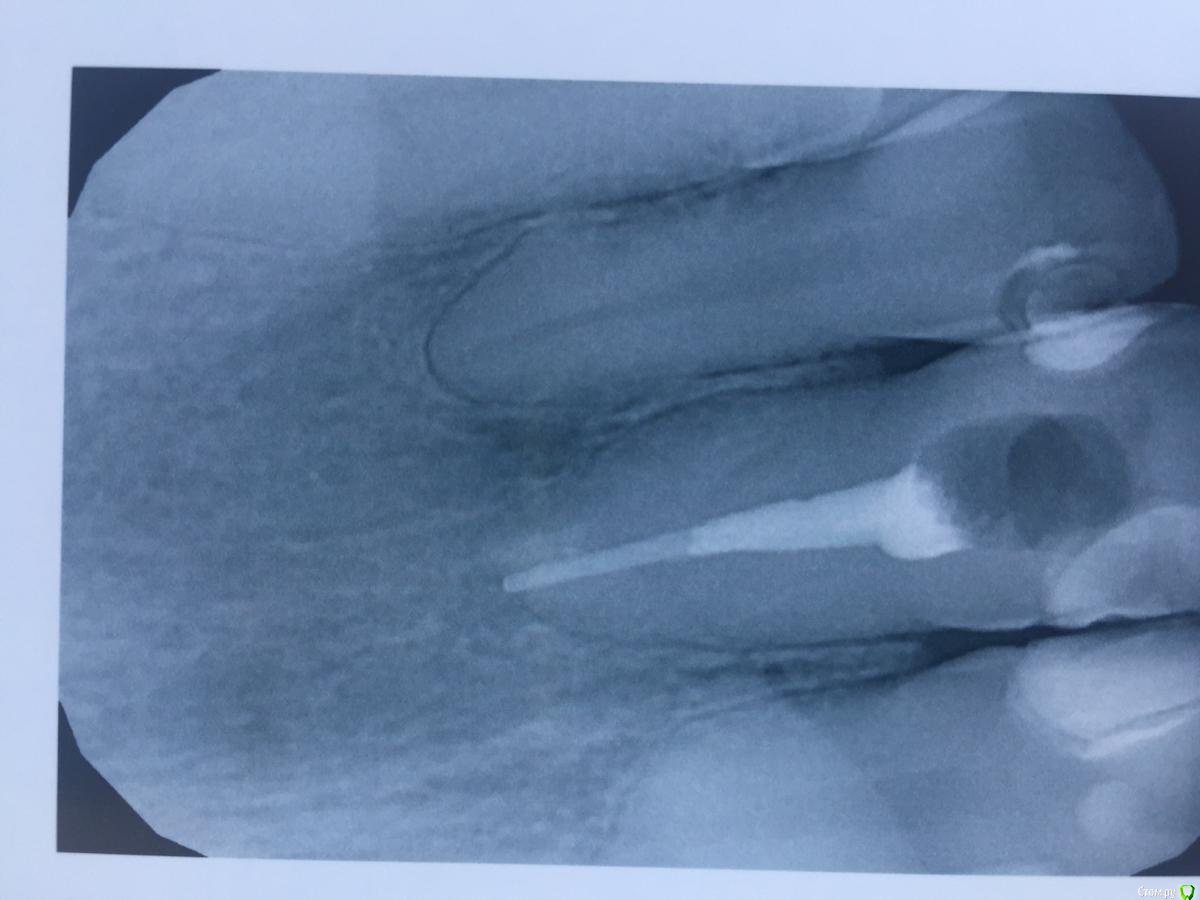

alina39 Опубликовано 9 декабря, 2016 Автор Поделиться Опубликовано 9 декабря, 2016 (изменено) Сделали новую КТ, подтвердился диагноз кистогранулема, почти киста по размерам.В прикрепленных - скриншот кт зуба.А главное боль не проходит, промыли и кальций положили неделю назад а боль не унимается, болит как рана и изредка дергает немного.Был один светлый период - 3 недели назад - когда зуб открыли, сказали полоскать и он неделю после этого не болел совсем, а потом все по новой. Изменено 9 декабря, 2016 пользователем alina39 Ссылка на комментарий

alina39 Опубликовано 9 декабря, 2016 Автор Поделиться Опубликовано 9 декабря, 2016 (изменено) покажите снимки на стадии леченияДругих снимков нет, сначала делали рентген, но на нем кисты не было видно, и потом вот два КТ: первый скриншот - это КТ 3 дня назад, а два других - 3 недели назад. Изменилось ли что-то за эти 3 недели? Изменено 9 декабря, 2016 пользователем alina39 Ссылка на комментарий